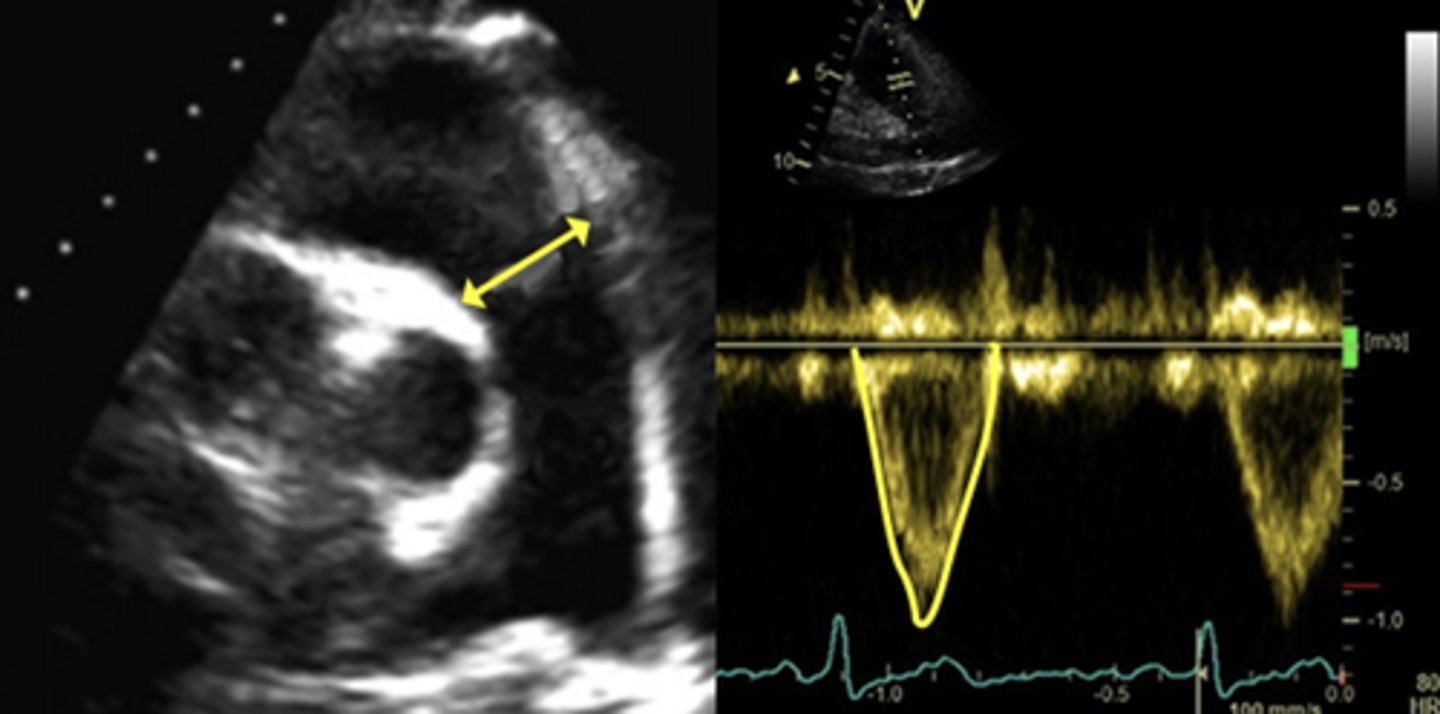

Pressure Half Time for PR

Calculated from deceleration time tracing of the slope

Shorter PHT = more severe PR

PHT or DT for Severe PR

< 100 msec or < 260 msec